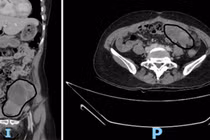

Mổ cắt gan, phổi cứu người đàn ông Campuchia bị ung thư phức tạp

Việc phối hợp hai cuộc phẫu thuật trong cùng chiến lược điều trị giúp vừa chẩn đoán chính xác, vừa xử lý triệt để nguồn bệnh.